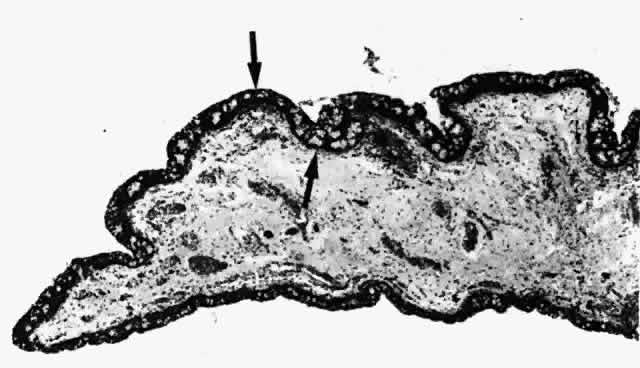

The lymphatic channels in the conjunctiva14 are arranged in two plexuses: (1) a superficial plexus consisting of small vessels placed below the capillaries; and (2) a deeper plexus consisting of larger vessels in the fibrous portion of the substantia propria (Fig. 21A and B). These vessels are important in the mediation of immunologic reactions that occur in certain ocular diseases and surgical conditions.

Fig. 21. A. Photomicrograph of bulbar conjunctival epithelium. Note goblet cells (arrow). The substantia propria is composed of loose connective tissue and diverse cellular elements. B. A lymph channel (L) in the substantia propria. The channel is lined with endothelial cells (arrows). (A and B, × 240)